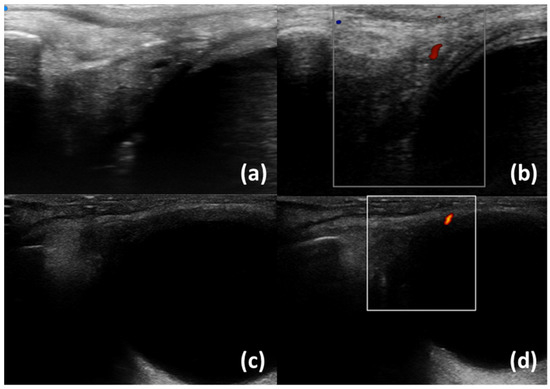

- Izzetti, R.; Ferro, F.; Vitali, S.; Nisi, M.; Fonzetti, S.; Oranges, T.; Donati, V.; Caramella, D.; Baldini, C.; Gabriele, M. Ultra-high frequency ultrasonography (UHFUS)-guided minor salivary gland biopsy: A promising procedure to optimize labial salivary gland biopsy in Sjögren’s syndrome. J. Oral Pathol. Med. 2021, 50, 485–491. [Google Scholar] [CrossRef]

- Aringhieri, G.; Izzetti, R.; Vitali, S.; Ferro, F.; Gabriele, M.; Baldini, C.; Caramella, D. Ultra-high frequency ultrasound (UHFUS) applications in Sjogren syndrome: Narrative review and current concepts. Gland. Surg. 2020, 9, 2248–2259. [Google Scholar] [CrossRef] [PubMed]

- Fulvio, G.; Donati, V.; Izzetti, R.; Fonzetti, S.; La Rocca, G.; Ferro, F.; Baldini, C. Correspondence between minor salivary glands ultra-high frequency ultrasonography and histology: A case report of severe/atypical lymphoid infiltrate in Sjögren’s syndrome. Ann. Rheum. Dis. 2022, 40, 2474–2475. [Google Scholar] [CrossRef]